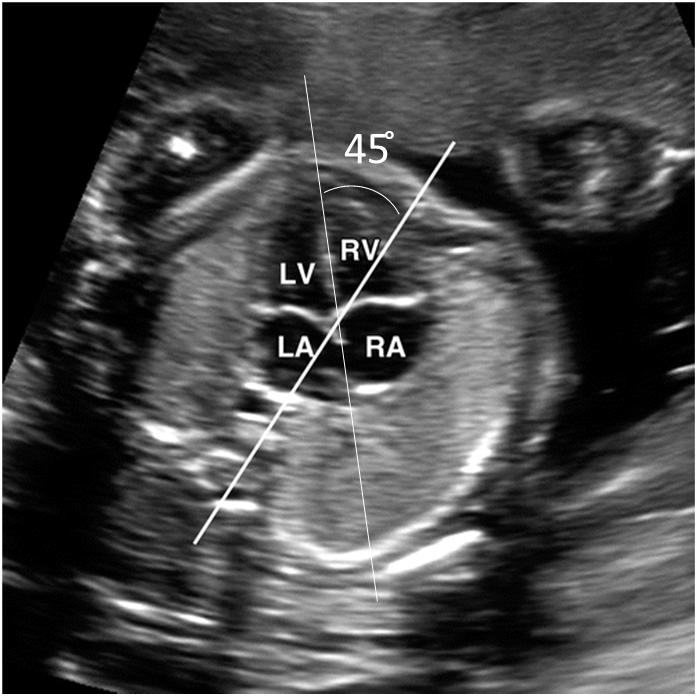

Identify structures of the heart

What view is this?

5 chamber view (used to recored aortic root, outflow, LVOT)

Crisscross view